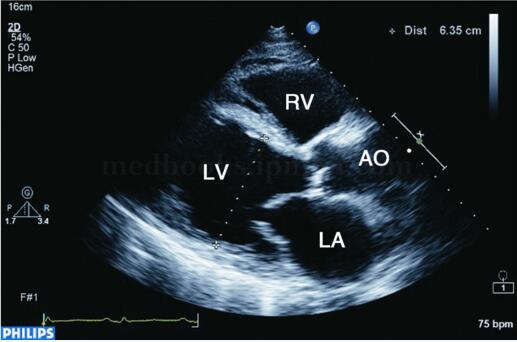

超声图片 如图2‐1‐178。

超声描述 左室下壁、后壁心肌变薄,约5mm,心肌回声增强,运动消失,其余节段心肌向心运动亦不同程度减弱,左心增大,左室略呈球形扩张,左室舒张末期内径63mm,左室泵血功能减低,左室EF32%。二尖瓣环扩张,探及中度二尖瓣反流。

超声诊断 左室下后壁心肌节段变薄、运动消失,其余节段运动减弱,符合缺血性心肌病改变,左室泵血功能减低,二尖瓣中度反流,提示乳头肌功能不全。

图2‐1‐178 左室长轴切面显示左心扩大,左室呈球形扩张

二维超声表现为左室显著扩大,几何形变,可呈球形扩张(见图2‐1‐179),左室心肌节段变薄,回声明显增强,运动明显减弱或消失,室壁增厚率消失,并伴有左室壁普遍运动减弱和不协调,左室泵血功能明显减低(见图2‐1‐180),二尖瓣开放幅度减低。左室腔内血流速度常较缓慢,有时可见附壁血栓形成。